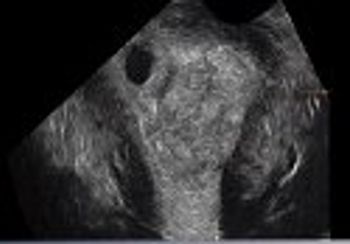

Challenge your diagnostic skills: Are these normal findings?